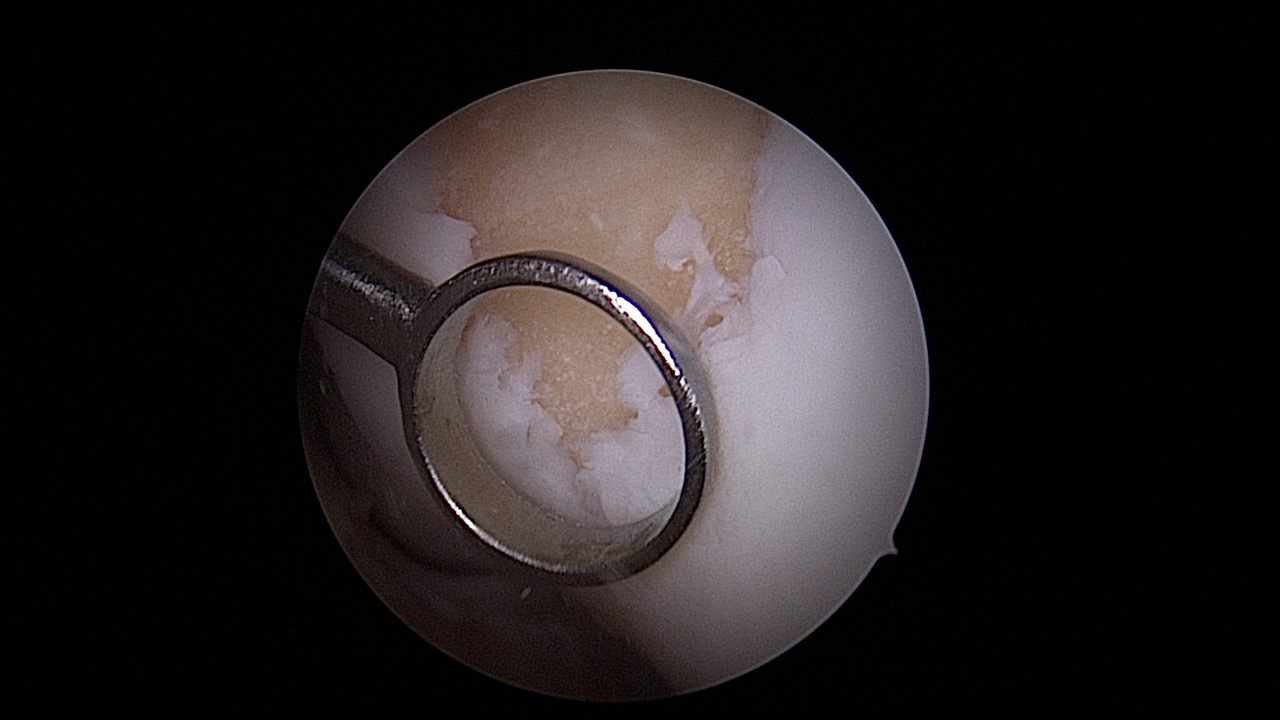

#049: Lateral Unicondylar Knee Replacement PSI

Surgery and Comments: Roland Becker

Provided by

Winglet

Date

Apr 2019

Format

TechTip

Price

0.99 €

Joint Replacement

Knee